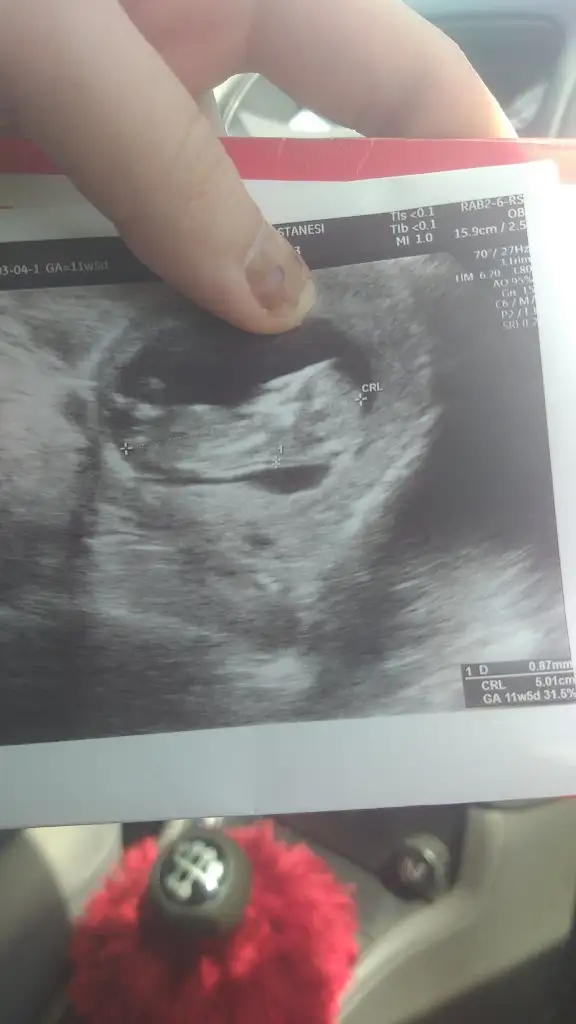

Erkek7+0 ultrasona göre tahmin alabilir miyim![]()

Öncelikle teşekkürler. Hayırlısını istiyorum ama bi kızım var birde oğlum olsun isterdim suan 9+3 bakalım belli olsun yazıcam buraya

12+4 bakar musun cnm birRamzi teorisini ilk defa duyuyorum ama bence bebeğin kız.